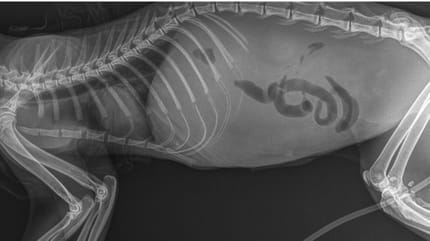

Bei der feuchten Form vermehren sich die Viren im Blut dauerhaft. Der Grund dafür ist die schwache Reaktion des Immunsystems. Es kommt zu einer Entzündung der Blutgefäße. Beim Fortschreiten der Krankheit sterben Zellen und Gewebe ab. Infizierte Flüssigkeit tritt aus und verbreitet sich im Körper der Katze.

Die trockene Form zeichnet sich durch einen milden Verlauf aus. Dies liegt an einem stärker reagierenden Immunsystem. Bei erkrankten Katzen bilden sich entzündliche Knoten in den Organen aus. Im Vergleich zur feuchten Form kommt es bei den knotigen Veränderungen zu keinem Flüssigkeitsaustritt.